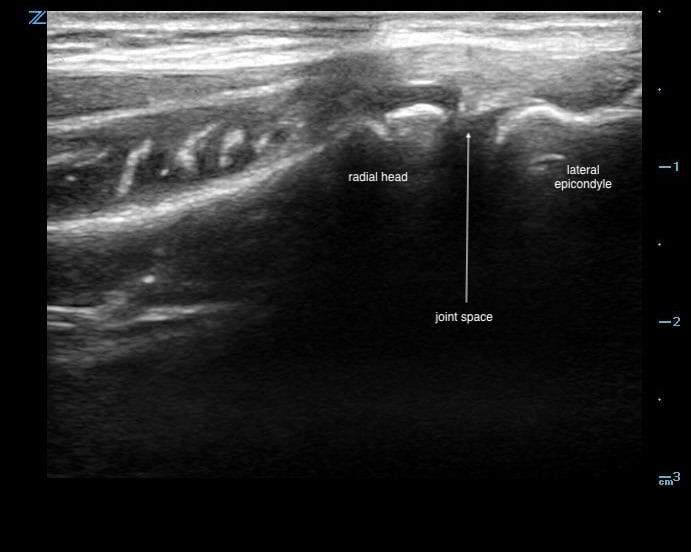

Elbow

- On the lateral aspect of the elbow, key structures are the capitellum at the lateral epicondyle and its articulation with the radial head distally.

- The common extensor tendon can appear superficially.

- An effusion appears hypo/anechoic within this joint space.7

- Lateral approach preferable for arthrocentesis

- Linear transducer

- Laterally against the proximal forearm parallel to the radius shaft (Fig. 10)

- Figure 10. Transducer placement for elbow arthrocentesis

- Scan proximally to the lateral epicondyle to visualize the space between the radial head and lateral epicondyle.7 (Fig. 11)

- Figure 11. Ultrasound demonstrating normal radiohumeral joint space

- An effusion is an anechoic collection within this space. (Video 3, 4)